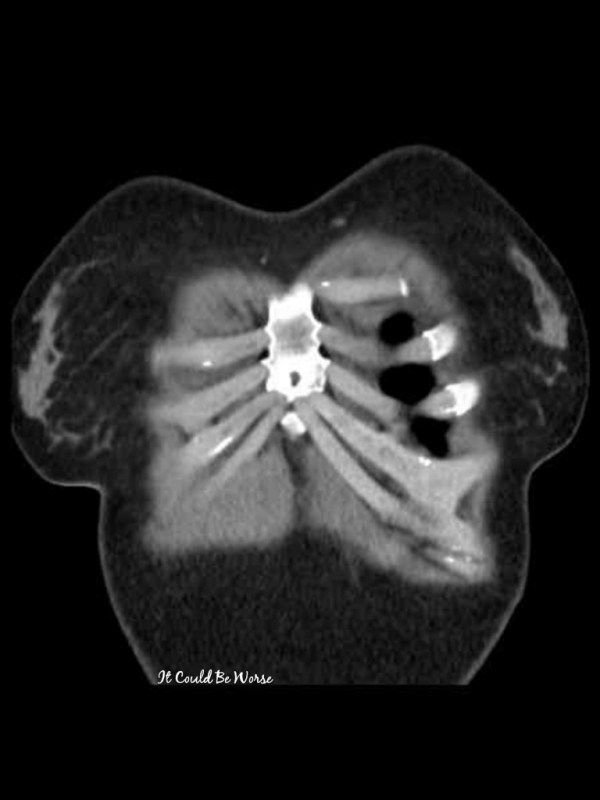

I am just a few days past my one-month post-op date and I just had what should be my last surgery for a while - my right-hand tendon sheath release for De Quervain's Tenosynovitis. A month ago, I had more work done on my wonky ribs. With two new incisions, that makes seven scars on... Continue Reading →

Long story short - Thoracic surgery is confirmed for Wednesday - with my COVID test #1. Then, just shy of 2 weeks later, I'll have my first surgery on my right hand - with my COVID test #2. Any way you slice it, June is really going to be fun for me. ๐ But anyway...... Continue Reading →